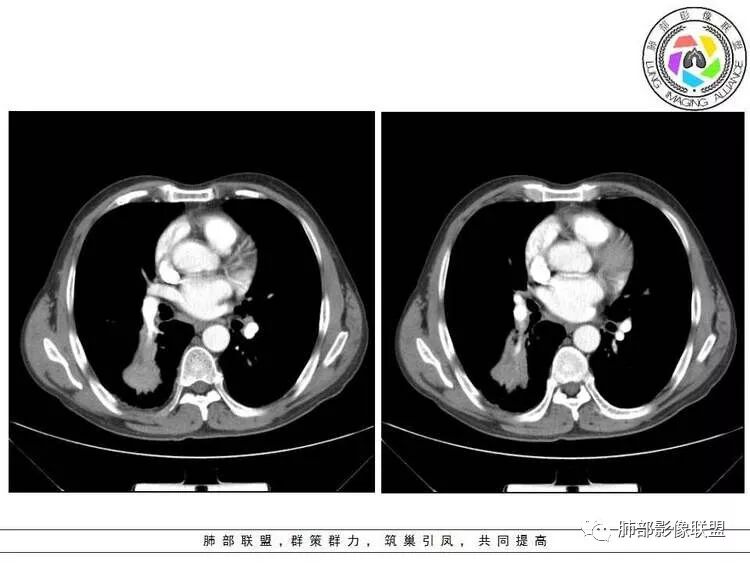

M-Imaging :病人胸痛20天,病灶三角形宽基底与胸膜贴近,肺门侧支气管通畅,造影显示肺动脉狭窄,考虑肺动脉栓塞,肺梗死?HeKate·Awizard·Sinitici:老师,请教一下,这是联盟讲座里说到的支气管爬行征吗?M-Imaging :我觉得像肺梗死,支气管通畅的采莲:中老年男性,右肺下叶背段片状影,边缘收缩平直,会不是异物可能么呢?中老年男性,咳嗽咳痰发热,急性起病,右肺下叶背段片状影,边缘收缩平直,周围有点片影,考虑异物合并感染,鳞癌待排。南边:多种意见:肺梗死、结核、异物、鳞癌肺动脉还好吧

南边:紧贴着斜裂过来的一个病灶,它的特点是:外围大,内带小。它整个下叶背段体积与对侧相比稍微缩小一点,但是缩小地不是很厉害。外支朝前下走了,仔细看血管,肺动脉走行自然,直达远端。远端实变区是肉芽肿成分,稍微有一点低密度,没有明显坏死,稍微有一点点坏死。而且附近有很多卫星灶,附近很多斑片影,有一些明显有气道壁增厚,细支气管炎的特点,还有就是下叶其他段很多斑片状影。换个角度,第一如果是肺癌,刚才看到PET-CT提示肺癌伴阻塞性肺炎,这个是不符合的。第二如果是肺癌阻塞性肺炎,近端血管肺动脉走行不会那么自然集聚的,这个是不符合的。理由是:如果这个病灶是肺癌,那么明显属于中央型肺癌,中央型肺癌的特点是近端大,远端小,近端是一个肿块,远端阻塞,远端阻塞是阻塞性炎症或者不张,它应该体积缩小,斑片状实变,不会这么密实。刚才有老师提到支气管,这个片有缺陷的地方,给的图像好像那层,如果把其他图像拿开再重叠一下。

如果是单纯看这幅图像,会觉得背段外侧支气管分支堵塞的,但是看下面这层图

南边:你就发现外侧支气管朝下走的分支非常自然,通畅的。

南边:这个肺门区,11区和7区都有一些淋巴结,淋巴结的形态不是类圆形,而是梭形的。这个病灶给的图比较少,个人倾向,第一强化非常均匀,肉芽肿性病变;第二,里面血管走行非常自然,远端大近端小,倾向炎性,特别是下面还有斑片状影,非阻塞远端,支气管远端病灶下叶背段,其他段也有,所以我倾向炎性;另外,它里面整个走行符合支气管树爬行征,我倾向结核可能,首先我定在炎性,其次有没有结核的可能。